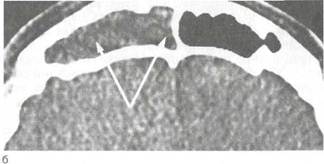

По характерным жалобам, данным анамнеза и объективного осмотра обычно не всегда удается установить диагноз. Для того чтобы достоверно дифференцировать острый гайморит от фронтита и этмоидита, а также определить особенности патологического процесса в пазухе, необходимо провести ряд дополнительных исследований: рентгенографию околоносовых пазух, которая в настоящее время является обязательным и достаточно информативным методом диагностики воспаления пазух (более подробно это описано в главе 1) или КТ (рис. 2.23). В некоторых случаях делают диагностическую пункцию с отсасыванием и контрастированием верхнечелюстной пазухи.

| Рис. 2.23. Методы лучевой диагностики патологии ОКОЛОНОСОВЫХ пазух. а — рентгенограмма околоносовых пазух в норме; б — рентгенограмма — гнойное воспаление верхнечелюстной пазухи; в — компьютерная томограмма — гнойный гайморит справа. |